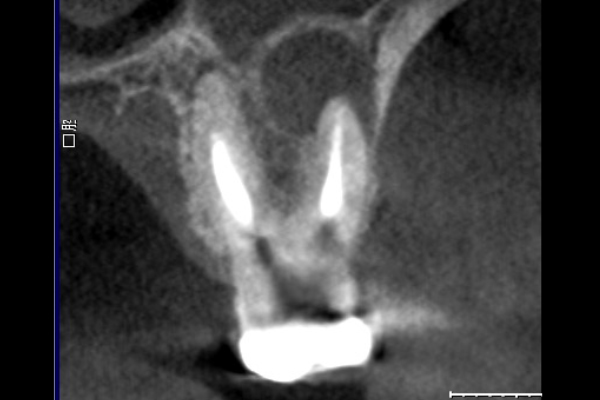

【札幌駅前】精密根管治療

60代男性の大臼歯(奥歯)の症例

- 主訴

- 「時々歯茎が腫れる」とのことでご来院されました。数週間前から症状があり、他の医院では「抜歯の可能性がある」と言われ、不安に感じていらっしゃいました。

- 期間

- 治療期間2ヶ月、治療回数3回、レントゲン写真で治癒を確認できるまでの期間6ヶ月

- 総額154,000円(税込)

- 治療内容

- 1.古い被せ物の除去と虫歯の徹底除去 まず、古い銀歯を外し、内部に広がっていた虫歯を丁寧に取り除きました。

2.マイクロスコープ下での根管治療 唾液などによる細菌の侵入を防ぐ「ラバーダム」を装着し、マイクロスコープ(歯科用顕微鏡)で根管内を数十倍に拡大しながら治療を進めました。複雑な形状の根管の内部まで、汚染された組織を徹底的に洗浄・消毒します。

3.根管充填(こんかんじゅうてん) 根管内が完全にクリーンになったことを確認し、再感染を防ぐために専用の薬剤で隙間なく密閉しました。

4.土台と被せ物の作製 歯の強度を補うための土台を立て、最終的なセラミックの被せ物を作製し、装着しました。

- 治療に伴うリスク

- 少しでも汚染物質が残ると再発のリスクが高まります。